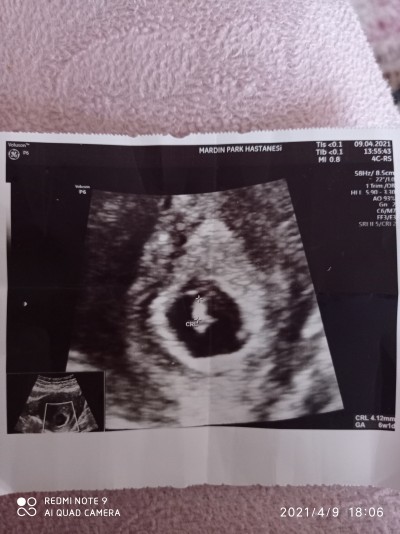

İlk ultrason fotoğrafı ve nereden bebek kaç haftalık yazıyor ve kese boyutu kaç haftalık

imagegorunuyor sizce